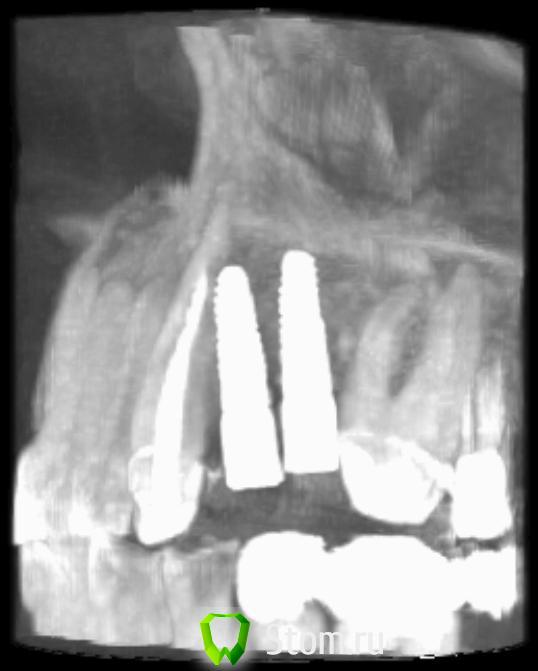

ern Опубликовано 15 апреля, 2012 Поделиться Опубликовано 15 апреля, 2012 Уважаемые господа, очень бы хотелось узнать ваше мнение по положению имплантов.Снимки сделаны через 6 месяцев, незначительно изменен ракурс.С уважением. Ссылка на комментарий

ern Опубликовано 16 апреля, 2012 Автор Поделиться Опубликовано 16 апреля, 2012 Добрый вечер! Спасибо за ответ. Меня интересует -насколько критичен контакт импланта с корнем 3 зуба-будут ли проблемы с протезированием из-за отклонения по осям и расстояния Диаметр 3,4 С уважением. Ссылка на комментарий

Sahan Опубликовано 16 апреля, 2012 Поделиться Опубликовано 16 апреля, 2012 Добрый вечер! -насколько критичен контакт импланта с корнем 3 зуба-будут ли проблемы с протезированием из-за отклонения по осям и расстояния Диаметр 3,4 С уважением.1) Время покажет, все зависит от наличия очага воспаления в этой области.2) Проблемы с протезирование будут и периимплантит будет. Ссылка на комментарий

Sahan Опубликовано 16 апреля, 2012 Поделиться Опубликовано 16 апреля, 2012 Да вы сами посмотрите на снимок. Имплантаты стоят слишком близко друг к другу плюс криво - отсюда и сложности. А решение только радикальное: удалить импл, костная пластика и повторная установка но уже в правильном положении и с соблюдением правила 1,5-3-1,5. Ссылка на комментарий

Bier Опубликовано 17 апреля, 2012 Поделиться Опубликовано 17 апреля, 2012 квалифицированный подход как раз таки предполагает удаление таких имплантатов. надо смотреть в полости рта на счет возможности удаления только 1 имплантата. Пока даже неясно какой объем пластики потребуется, соответственно о прогнозах говорить рановато. правило 1,5мм между имплантатом и зубом и 3мм между имплантатами - минимальные расстояния, при их нарушении будут проблемы. Ссылка на комментарий